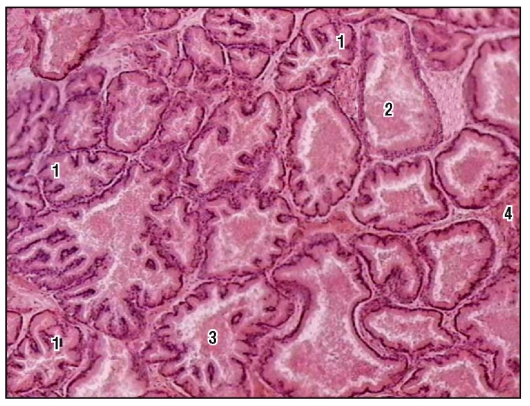

Исследование: микропрепарат молочной железы в медицине

Раздел: Снимки-откровения